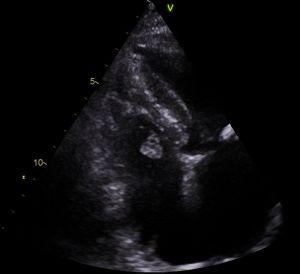

An echocardiogram is often requested for patients experiencing chest pain, and this imaging modality lends itself perfectly for the detection of myxomas.

Above: a rare finding of a myxoma on the right side of the heart in a patient referred for a suspected myocardial infarction. In this instance, the myxoma moves with opening of the tricuspid valve into the right ventricle during diastole, and returns to the right atrium during (ventricular) systole. This can be appreciated from the images below, where the image on the left is taken in diastole, and the image on the right during systole: